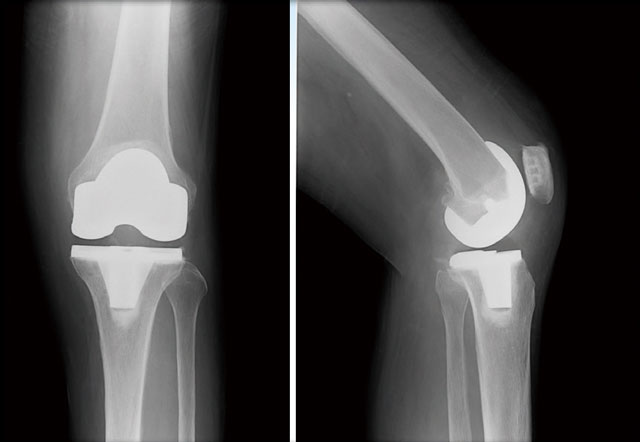

人工膝関節全置換術後のレントゲン

人工膝関節置換術には、関節表面を全部入れ替える全置換術と内外側や前方など悪い部分だけを入れ替える部分置換術の2種類があります。当院では最近は部分置換術が増えていて、この手術が従来の骨切り術のような位置づけになる可能性があると考えております。

部分置換術は、変形は一部のみでじん帯もしっかりしており、可動域もよいという患者さんに行っています。将来、置換していない部位の軟骨がすり減ってくることもありますが、その場合は全置換術で対応可能です。部分置換術は全置換術に比べ、傷口の範囲が小さく手術時間も短い、出血や侵襲も少ない、そして、感染症や血栓など合併症のリスクも少なく、離床は早いし入院期間も短いなどメリットがたくさんあります。このほか、部分置換術では前・後十字じん帯などが温存されるので、より自然な動きを感じやすく、膝の曲りも良いのが特徴です。

部分置換術でもO脚は少し治ることが多いですが、全置換術はO脚を完全にまっすぐにできます。また長期成績も全置換術が優れ、全置換術だと10年で9割、15年で8割、部分置換術では10年で8割、15年で7割ほどは長持ちするといわれております。